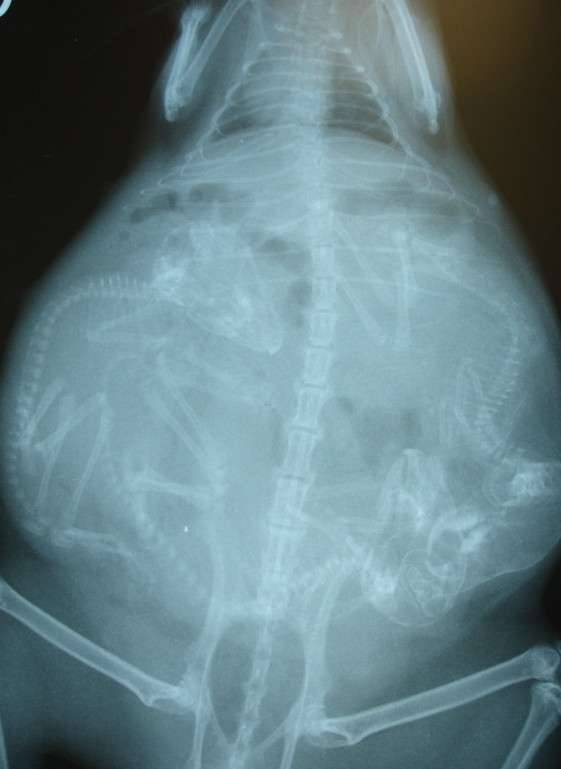

▼怀孕的猫咪